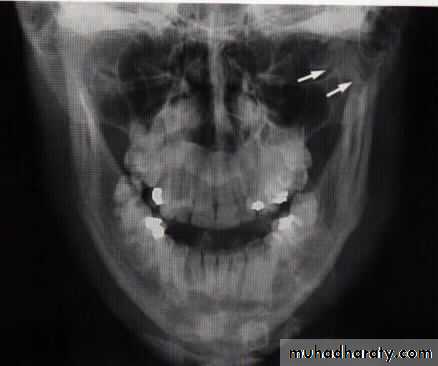

Plain radiographOPG

Lateral oblique

PA mandible

AP mandible (reverse Townes)

Lower occlusal

CT scan

3-D CT imaging

MRI

Fracture mandible in children

Close reduction

Open reduction and fixation

Plating at the inferior border

Resorpable plates